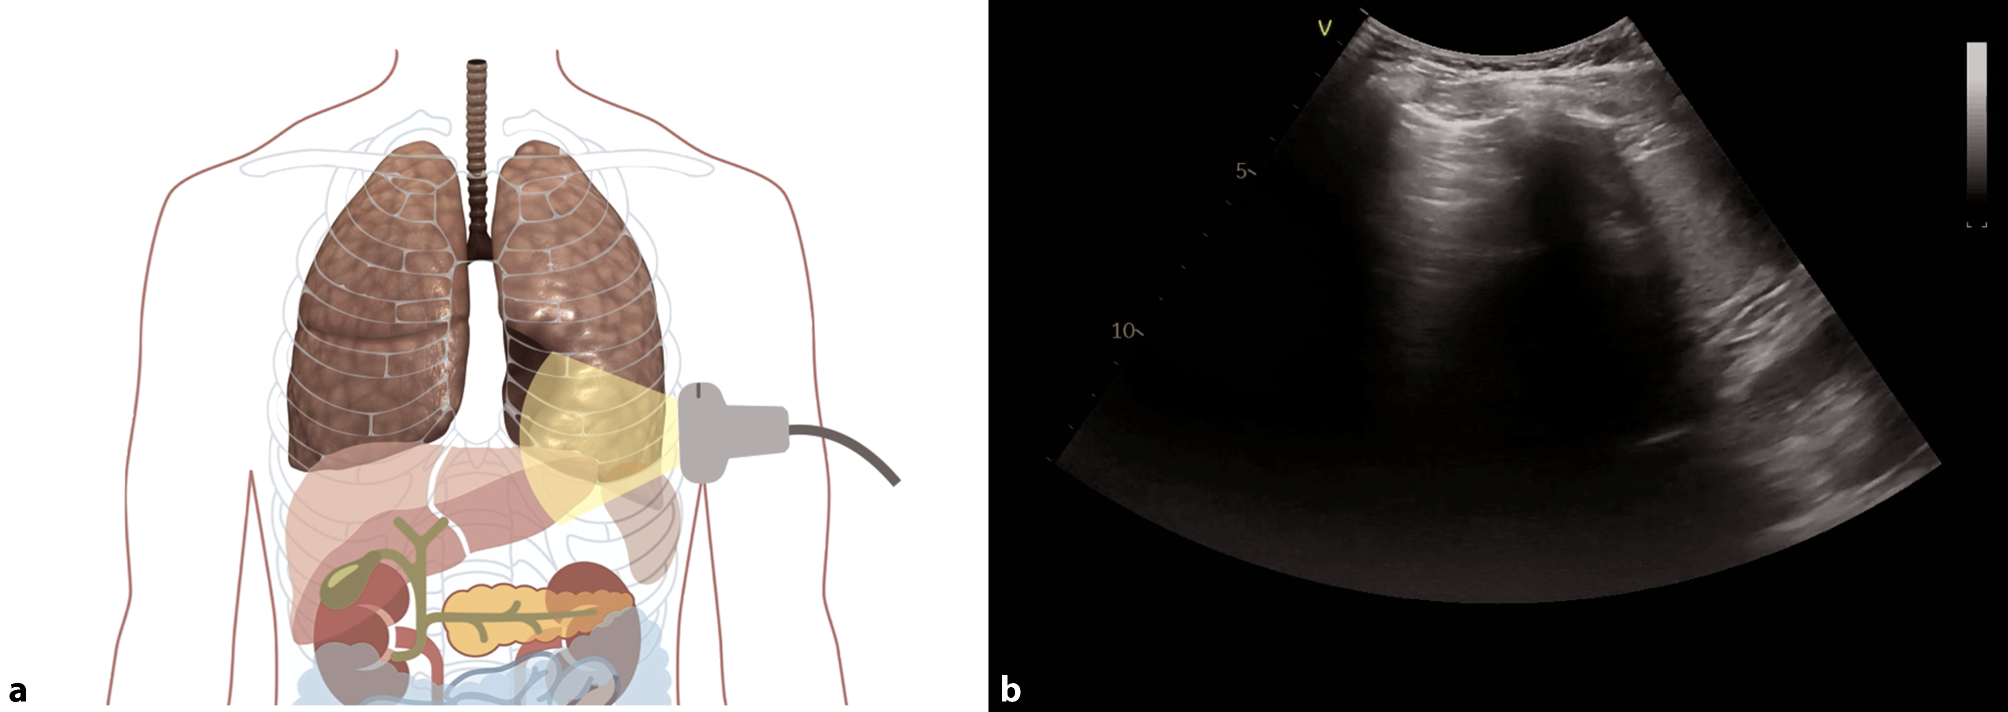

Fig. 9

Evaluation for pleural effusion—right hemithorax. a Schematic of the right sided approach. b Normal sonographic anatomy without pleural effusion

Bild vergrößern

Fig. 10

Evaluation for pleural effusion—left hemithorax. a Schematic of the left-sided approach. b Normal sonographic anatomy without pleural effusion

Pleural effusions are reportedly rare in COVID-19 pneumonia, and thus indicate a bacterial superinfection or heart failure [26]. To detect pleural effusions in supine patients, e.g. in an ICU, we recommend scanning the posterior regions with a convex or cardiac transducer as posterior as possible (Figs. 9 and 10). In an upright patient, the posterior regions—zone six (Fig. 8)—can be visualized with a convex or cardiac transducer to identify pleural effusions. In large pleural effusions, compression atelectasis can be visualized. Likewise, as previously mentioned, differential diagnoses of pleural effusions have to be considered [39]. The suspicion of heart failure is further supported by the presence of reverberation artifacts, which arise from a non-fragmented pleural line (B-lines). These B‑lines arise from the smooth pleural line in a bilateral homogenous way, not fading until the end of the screen, moving with pleural sliding and erasing other artifacts (A-lines). The presence and quantity of B‑lines correlate with the severity of clinical presentation of patients [24, 35, 40].